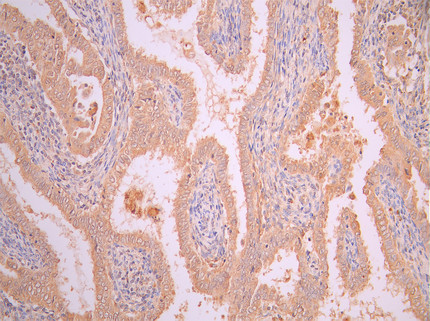

5. FAP研究工具

FAP作為腫瘤微環(huán)境中的關(guān)鍵靶點(diǎn),其在腫瘤的侵襲、轉(zhuǎn)移、免疫逃逸以及耐藥性中發(fā)揮重要作用。華美生物提供FAP重組蛋白、抗體及ELISA試劑盒產(chǎn)品,助力您開(kāi)發(fā)特異性靶向FAP的藥物,探索其在腫瘤治療中的應(yīng)用潛力。